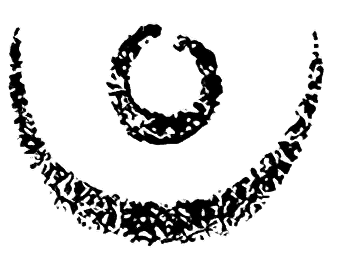

Bild: Mutterkorn an Roggen. Ausgangsprodukt der LSD-Synthese ist Mutterkorn.

Mutterkorn wurde zeitweilig im Auftrag und Vertrag mit der pharmazeutischen Industrie durch Impfung von speziell kultiviertem Roggen angebaut.

Entsprechende Anbauverträge der Firma Sandoz AG Basel belegten in den 60er Jahren ein Fläche von über 600 ha in der Schweiz. Der Höchststand der Vertragsfläche war mit 952 ha im Jahr 1955. Das Hauptanbaugebiet war in feuchtkühlen Gebieten des Emmentals und angrenzenden Gegenden, wo die Impfung des Roggens besonders gut gelang.

Der sehr arbeitsintensive Anbau auf kleinsten Flächen hat vielen kleinen Betrieben in diesen Gegenden zu einem willkommenen Zusatzverdienst verholfen. Mit dem Einsatz von speziell konstruierten Impf- und Erntemaschinen wurden die Anbauflächen pro Betrieb zusehend grösser und in das Flachland verlegt.